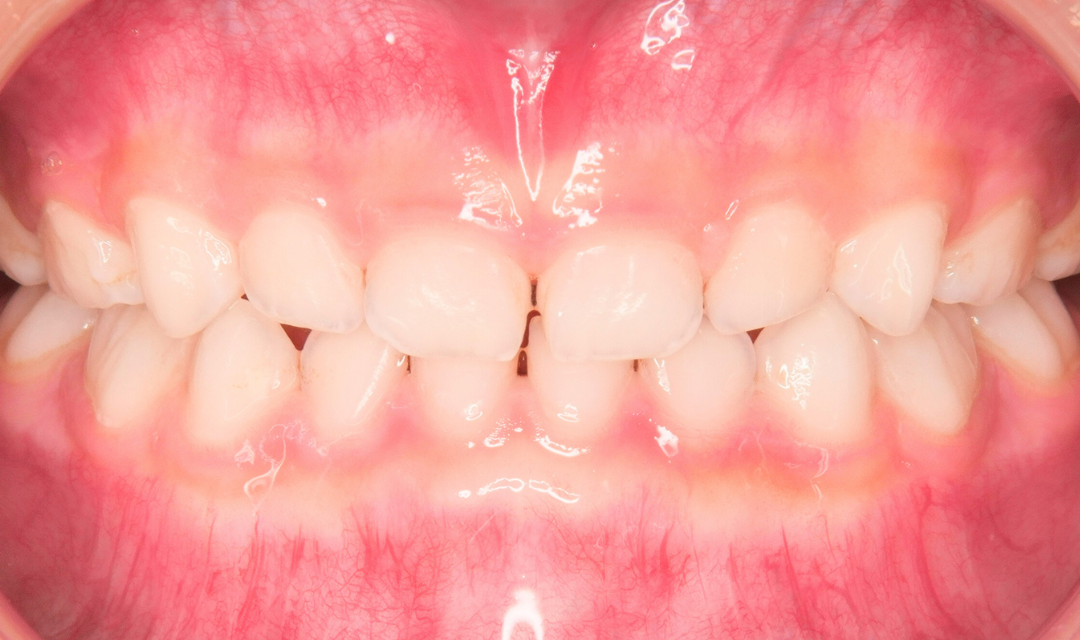

プレオルソによりわずか3ヶ月で反対咬合の改善が見られました。

開始から3か月で、前歯の噛み合わせに変化が見られました。

親御さんからは「もう反対咬合が治ってびっくりしています」というお言葉もありました。